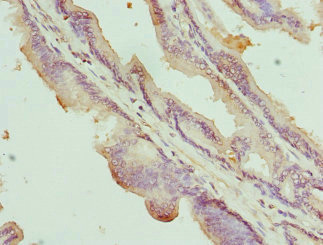

Immunohistochemistry of paraffin-embedded human prostate cancer using CSB-PA138304ESR2HU at dilution of 1:100